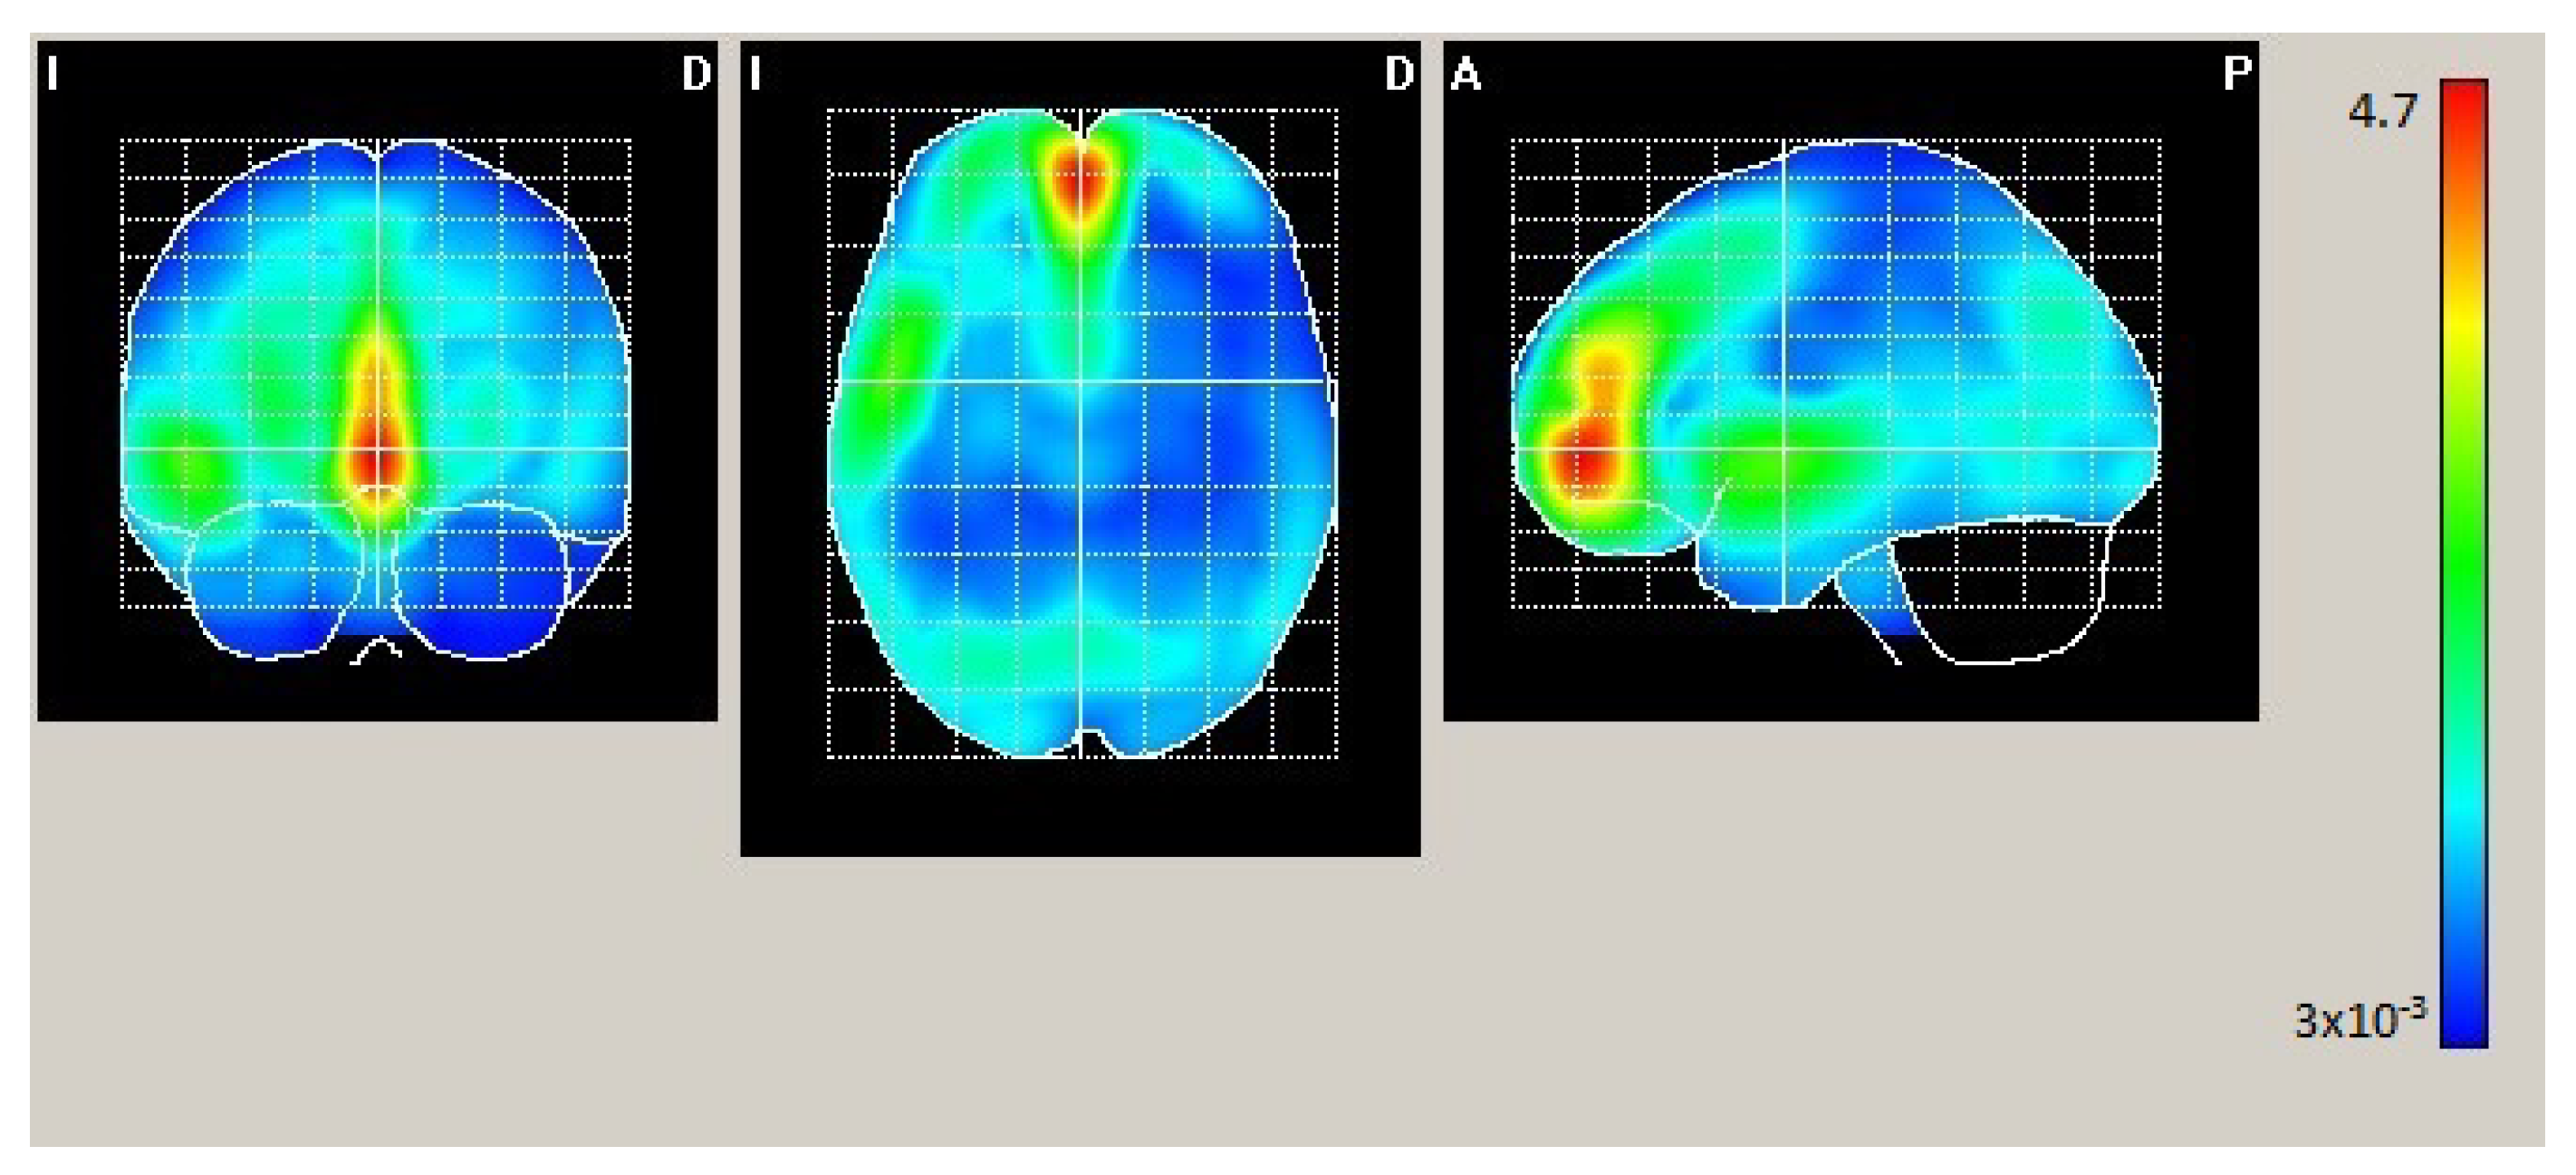

| AAL | X | Y | Z | Act. [µA/m] |

|---|---|---|---|---|

| Frontal_Mid_Orb_L | −2 | 54 | −4 | 2.631 |

| Frontal_Mid_Orb_R | 2 | 54 | −4 | 2.590 |

| Frontal_Sup_Medial_L | −2 | 54 | 0 | 2.586 |

| Cingulum_Ant_L | −2 | 50 | 0 | 2.568 |

| Frontal_Sup_Medial_R | 2 | 50 | 0 | 2.535 |

| AAL | X | Y | Z | Act. [µA/m] |

|---|---|---|---|---|

| Frontal_Mid_Orb_L | −2 | 50 | −4 | 2.407 |

| Temporal_Sup_L | −50 | −2 | −4 | 2.401 |

| Frontal_Mid_Orb_R | 2 | 50 | −4 | 2.39 |

| Cingulum_Ant_L | −2 | 50 | 0 | 2.382 |

| Frontal_Sup_Medial_R | 2 | 50 | 0 | 2.364 |

| Frontal_Sup_Medial_L | −2 | 54 | 0 | 2.352 |

| Temporal_Pole_Sup_L | −50 | 6 | 0 | 2.254 |

| Insula_L | −46 | 6 | −4 | 2.249 |